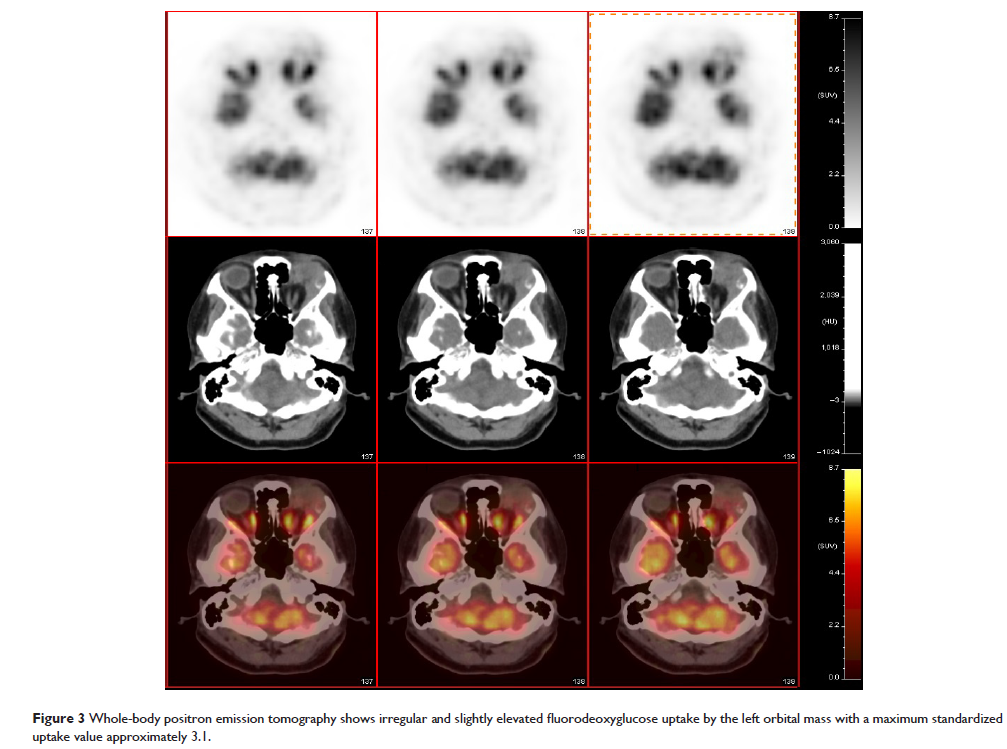

- 作者:Miao-Miao Zhu, Hong-Guang Cui, Xiao-Dong Teng

- 期刊:OncoTargets and Therapy